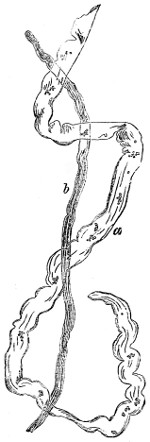

| Hæmatin Crystals, | 61 | |